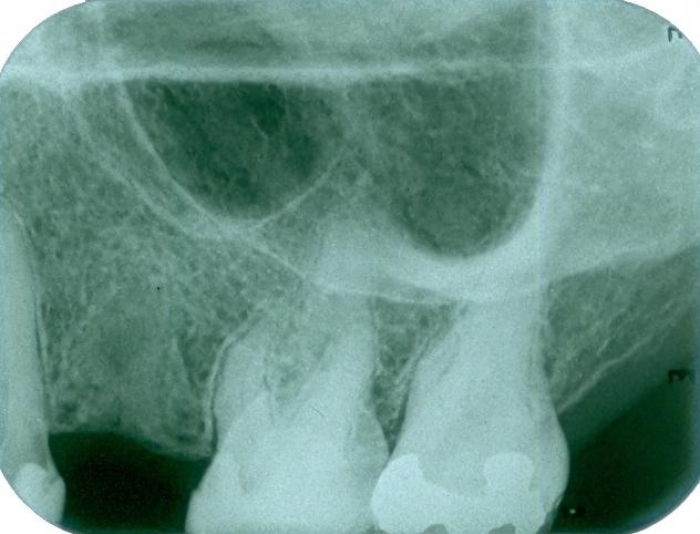

Raio X após a extração